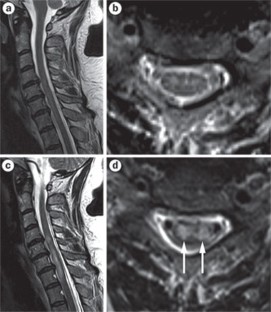

Longitudinal extensive transverse myelitis (LETM) is defined as a spinal cord lesion that extends over three or more vertebrae, as seen on MRI of the spine. The clinical presentation of a patient with LETM is often dramatic and can consist of paraparesis or tetraparesis, sensory disturbances, and gait, bladder, bowel and/or sexual dysfunction. LETM is a characteristic feature of neuromyelitis optica, but such spinal lesions can also occur in various other autoimmune and inflammatory diseases that involve the CNS—such as multiple sclerosis, sarcoidosis or Sjögren syndrome—or in infectious diseases with CNS involvement. Patients with a neoplastic disorder or traumatic spinal cord injury can also present with longitudinal spinal lesions. In this Review, the signs and symptoms that suggest various etiologies and differential diagnoses of LETM are described, and illustrated by educational case studies. The best therapeutic options for patients with each diagnosis are also discussed.

Evaluation of a patient with LETM should include MRI of the spinal cord and the brain, investigation of cerebrospinal fluid, and detection of cause-specific markers in the blood